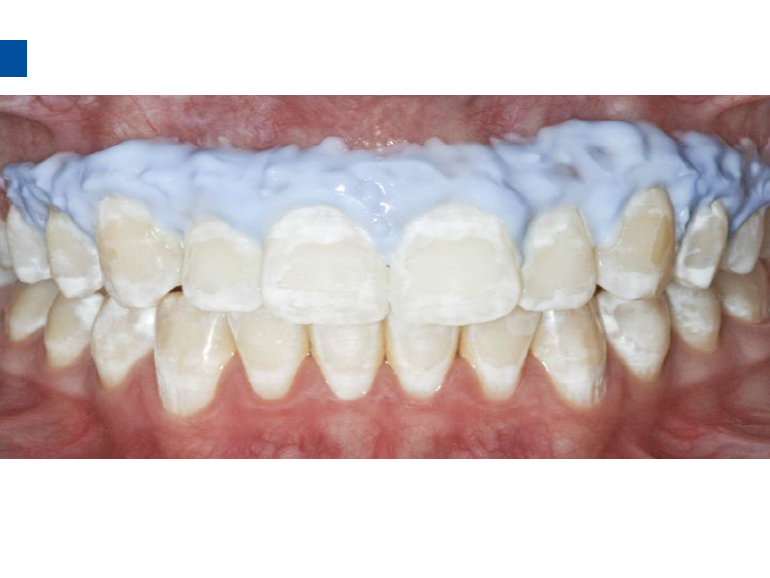

二、爱康渗透树脂唇颊面装Icon Caries Infiltrant – vestibular,治疗唇颊面釉质早期龋。(整个套装包含一次治疗两至三个早期龋损所需的材料。一次性使用,如果邻牙有类似病变可一并治疗)。

3、小心旋转注射器柄部,将足量材料涂布于龋损区域之上,等待2分钟,并用棉球去除多余材料,酸蚀范围应至龋损外2mm处,如果正畸患者托槽取下后发现牙面大范围早期龋损则需酸蚀整个牙面。(单手可完成注射器操作)。

7、旋转注射器柄部将足量材料涂布于已被酸蚀的龋损表面之上,等待3分钟,并用棉球去除多余材料。不要在牙椅照明灯直射下在前牙唇面涂布树脂。)

9、将一新的注射头装在含爱康渗透树脂Icon-Infiltrant的注射器上,重复步骤7-8.等待1分钟,光照40秒。